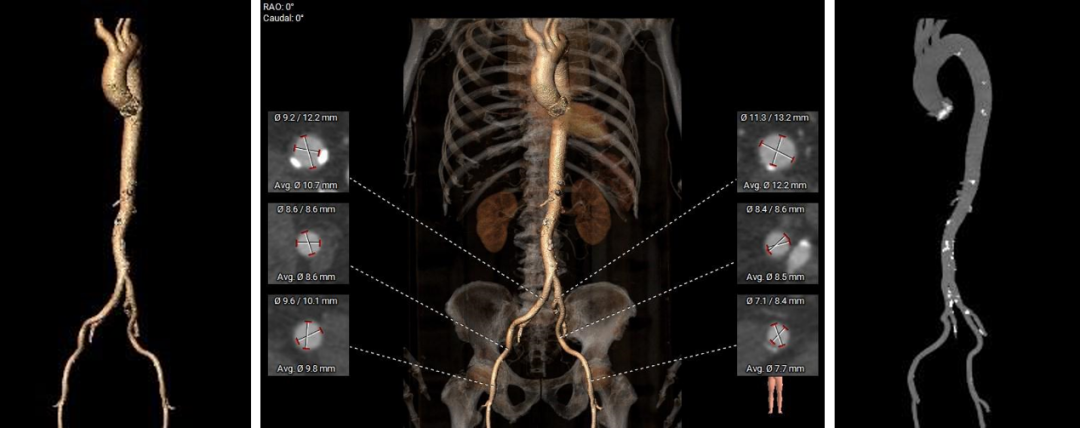

弓部及入路评估

入路血管:双侧髂股动脉明显扭曲,双侧髂总及弓部散在钙化,双侧入路血管直径良好。